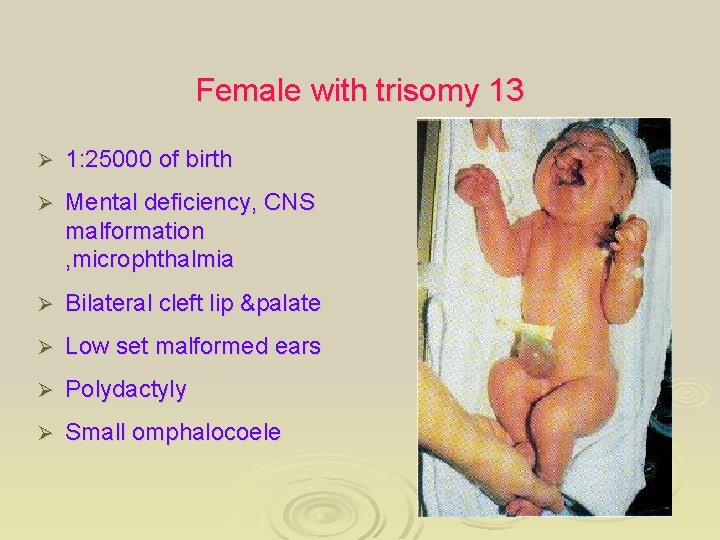

Female with trisomy 13 Ø 1: 25000 of birth Ø Mental deficiency, CNS malformation , microphthalmia Ø Bilateral cleft lip &palate Ø Low set malformed ears Ø Polydactyly Ø Small omphalocoele